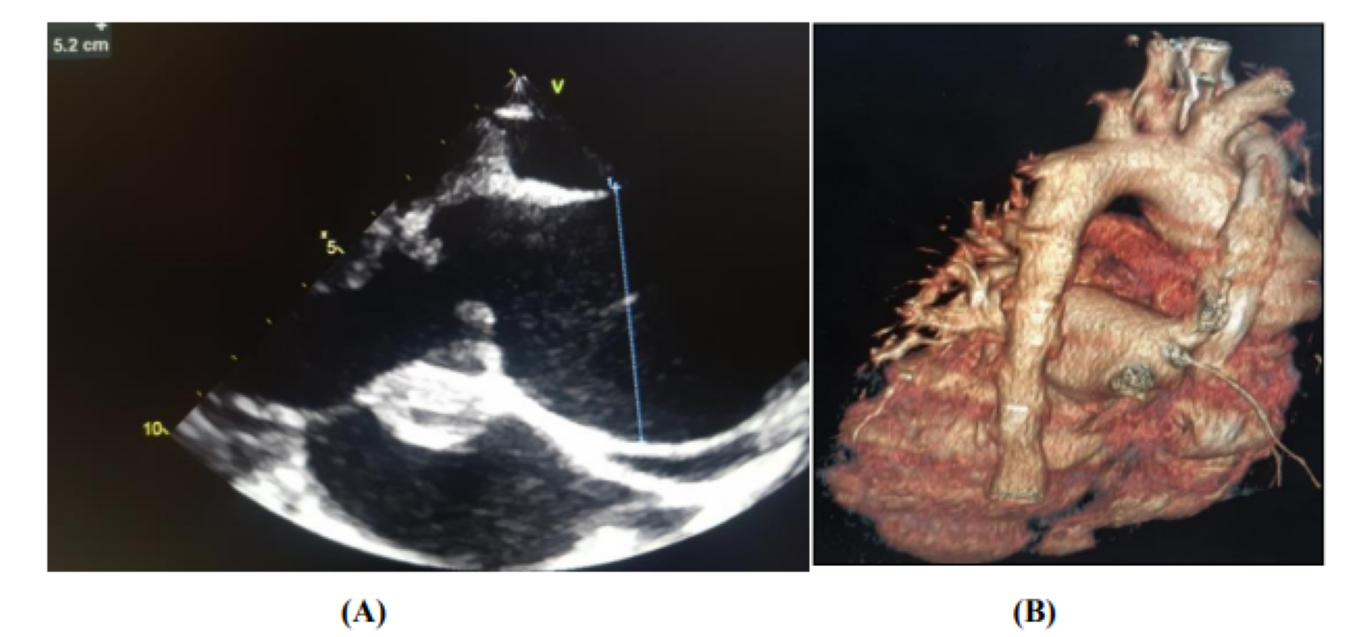

On transthoracic echocardiography, we find an aspect of valvular dilated cardiomyopathy with the presence of 2 vegetations at the level of the aortic valve (Figure 2), severe aortic insufficiency on the bicuspid aortic, and an aneurysmal dilation of the ascending aorta (52 mm), (Figure 3) complicated by an abscess collected at the level of the mitral aorto trigone and a 2nd abscess between the Left and Right cusps of the aortic valve fistulized into the aorta (Figure 4).

Figure 3: Appearance of aneurysmal dilation of the ascending aorta [Parasternal long axis on ETT (A), 3D reconstruction of chest CT angiography (B)]